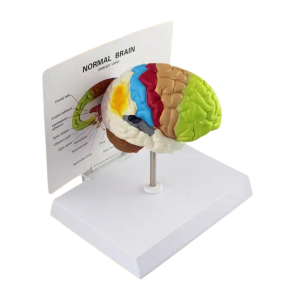

- Kadın Pelvik Taban Anatomisi: Kadın Pelvik Taban Maketi Model 38, kadın üreme sistemi, pelvik kaslar ve pelvik taban yapıları hakkında bir anlayış sağlar. Bu model, pelvik kasların yerini, fonksiyonlarını ve mevcut olan detaylı bir şekilde gösterir. Gerçekçi anatomi ve ayrıntılı tasarım , eğitim ve klinik kullanımlar için mükemmel bir araçtır.

- Gerçekçi Tasarım ve Ayrılabilir Parçalar: Modeldeki pelvik taban yapıları, yapının ayrıntılarıyla hazırlanmış olup, daha iyi görülebilmesi için genel ve ayrıntılı incelenebilir parçalar içerir. Bu sayede kadın pelvik yapıları hakkında bir eğitim sağlandı. Pelvik kasları ve organları doğru bir şekilde birleştirme ve yerleştirmelerini oldukça basittir.